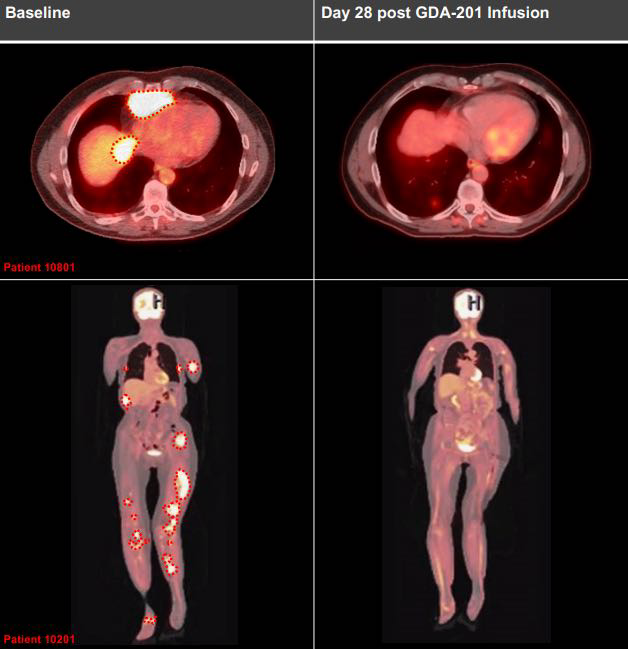

- 淋巴瘤治疗

:在GDA-201(一种NK细胞疗法候选药物)的临床试验中,7例B细胞淋巴瘤患者的肿瘤负担明显减轻,其中3例实现了完全缓解,即体内已检测不到肿瘤病灶。